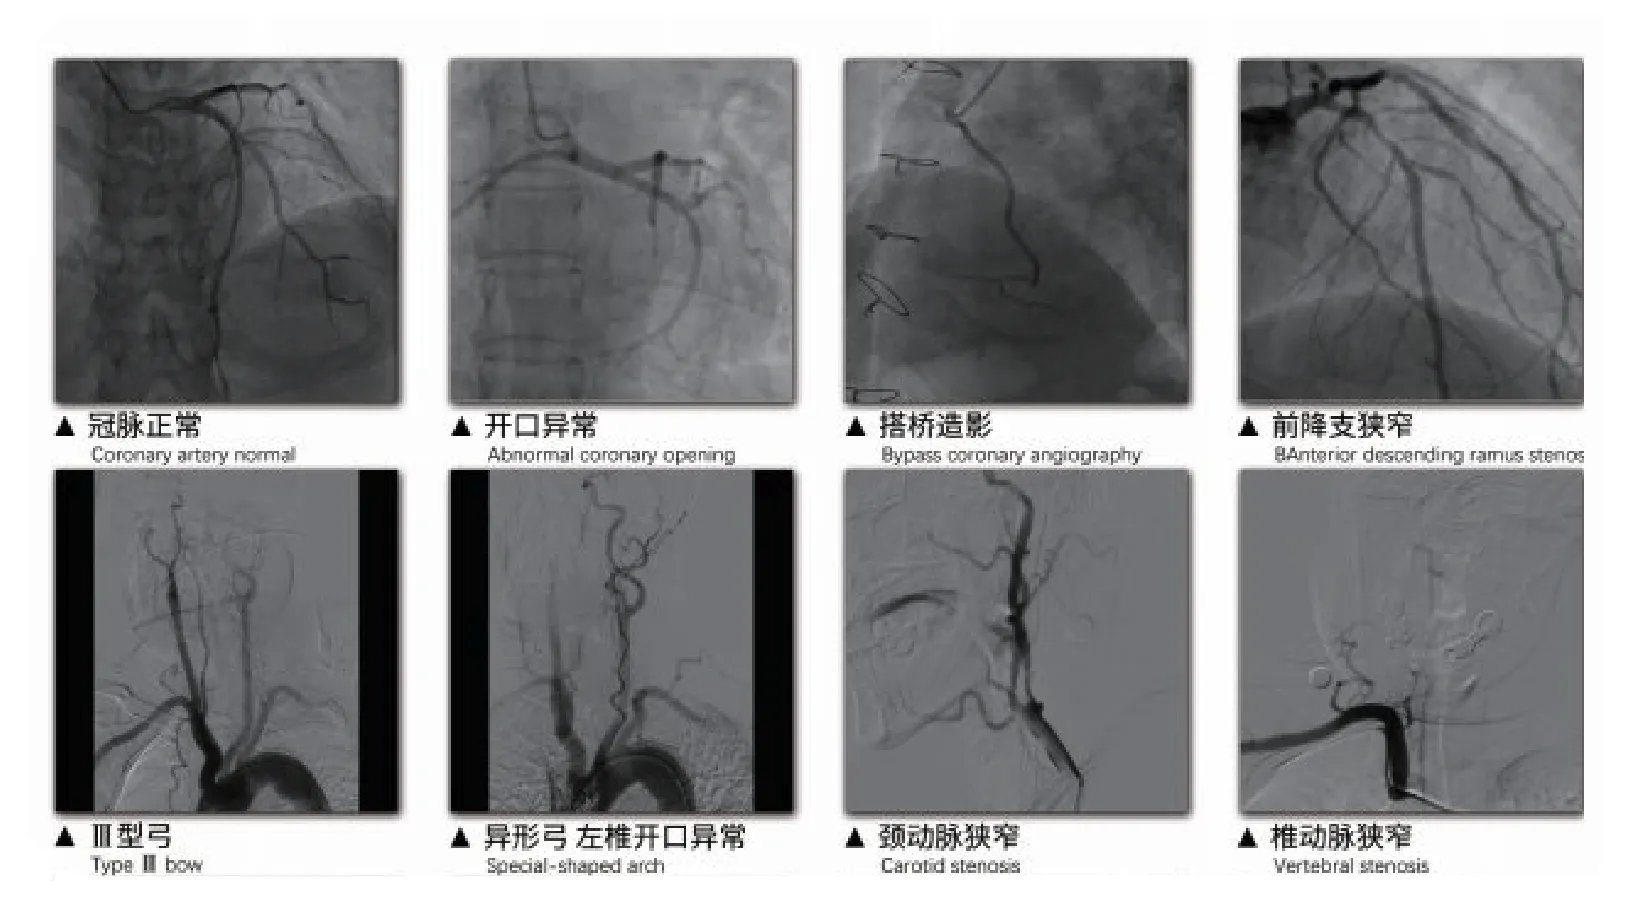

该模拟器由国内团队璞临医疗科技自主研发,基于先进的计算机虚拟仿真技术,结合真实临床病例精心设计,涵盖脑血管及心血管介入两大核心培训模块,可满足90%以上的心脑血管介入手术技能训练需求。系统内置丰富的心血管介入病例库,并支持病例更新与个性化定制,专为血管介入医师的实操培训打造,能够显著缩短临床医生的学习周期,助力其快速掌握规范化的手术操作流程与核心技巧。

涵盖多项心脑血管介入培训模块